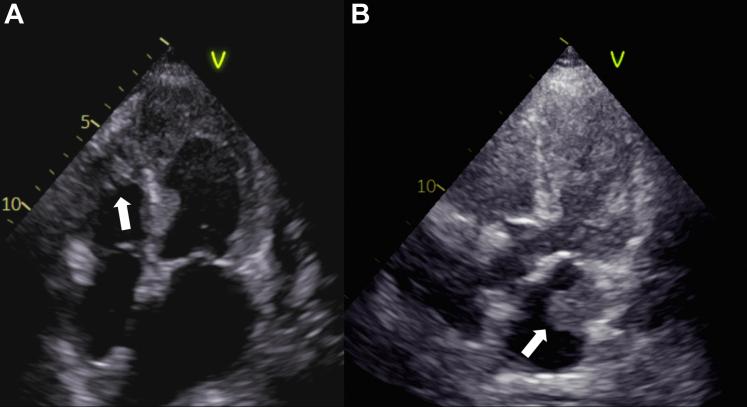

We present the case of an elderly woman with acute myocardial infarction involving diabetic ketoacidosis. Her transthoracic echocardiogram revealed multiple thrombi in both ventricles and left atrium. She was discharged from our hospital without experiencing complications, including thromboembolism, after receiving multidisciplinary treatment.

Multiple intracardiac thrombi are an uncommon complication of myocardial infarction. The ability of plain computed tomography to evaluate intracardiac thrombus is unknown.